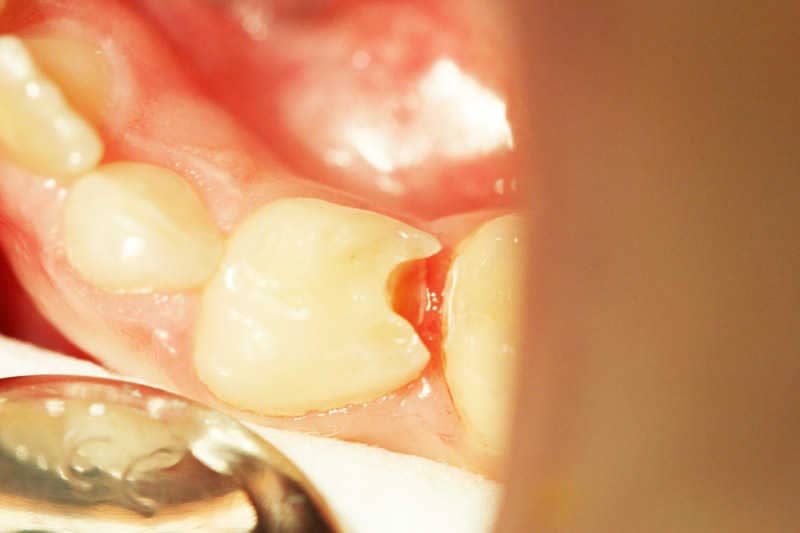

A szuvasodás eltávolítása után ez a kép látható. A cél minél több egészséges foganyag megőrzése a preparálás során - ez a minimál invazív eljárások lényege.

A szuvasodás eltávolítása után ez a kép látható.